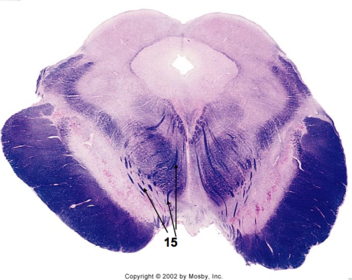

| Longitudinal pontine fibers (corticospinal tract) | |

| Transverse pontine fibers (dark fibers) | |

| Pontine nuclei (pale) | |

| Medial lemniscus | |

| ALS | |

| Trapezoid body | |

| Ventral trigeminothalamic tract | |

| Superior olive | |

| Central tegmental tract | |

| Facial nerve root fibers - descending | |

| Facial motor nucleus | |

| Interposed nuclei | |

| Medial longitudinal fasciculus | |

| Facial nerve root - internal genu | |

| Abducens nucleus | |

| Lateral vestibular nucleus | |

| Superior vestibular nucleus | |

| Inferior cerebellar peduncle | |

| Superior cerebellar peduncle | |

| Dentate nucleus | |

| Fastigial nucleus | |

| Anterior spinocerebellar tract | |

| Spinal nucleus of V | |

| Spinal tract of V | |

| Middle cerebellar peduncle | |